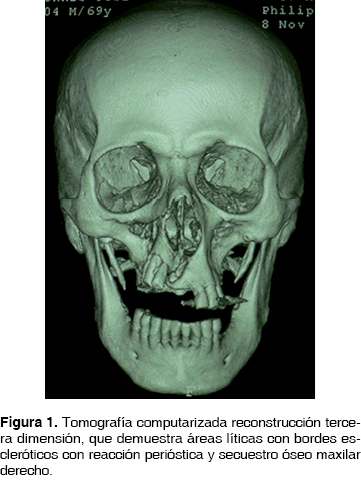

Clínicamente presenta una fístula en región de premolar superior izquierdo de 2 x 1 mm, halitosis severa, astenia, adinamia, cefalea holocraneana izquierda, enfermedad periodontal crónica, ausencia de múltiples órganos dentarios. La tomografía computarizada demuestra áreas líticas con bordes escleróticos con reacción perióstica y secuestro óseo (Figura 1). En biometría hemática presenta valores de hemoglobina de 14 g/dL, leucocitos de 7.44 cpm, glucosa de 109 g/dL. Se inicia tratamiento farmacológico con clindamicina 600 mg IV cada 8 hrs. y ceftriaxona 1 g IV cada 12 hrs. Se decide realizar hemimaxilectomía subtotal bajo anestesia general inhalatoria balanceada, mediante abordaje circunvestibular de 6 cm con disección de tejidos hasta exposición de la lesión, observando zonas de necrosis ósea, (Figura 2) obteniendo espécimen quirúrgico de 3 x 3 cm con áreas de necrosis de color negro y fétido. Se verifican macroscópicamente bordes óseos libres de lesión y se suturan los tejidos con sutura ácido poliglicólico 3 ceros.